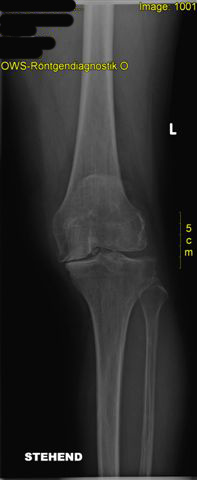

schwere Kniegelenksarthrose, Gelenksspalt innen komplett aufgebraucht